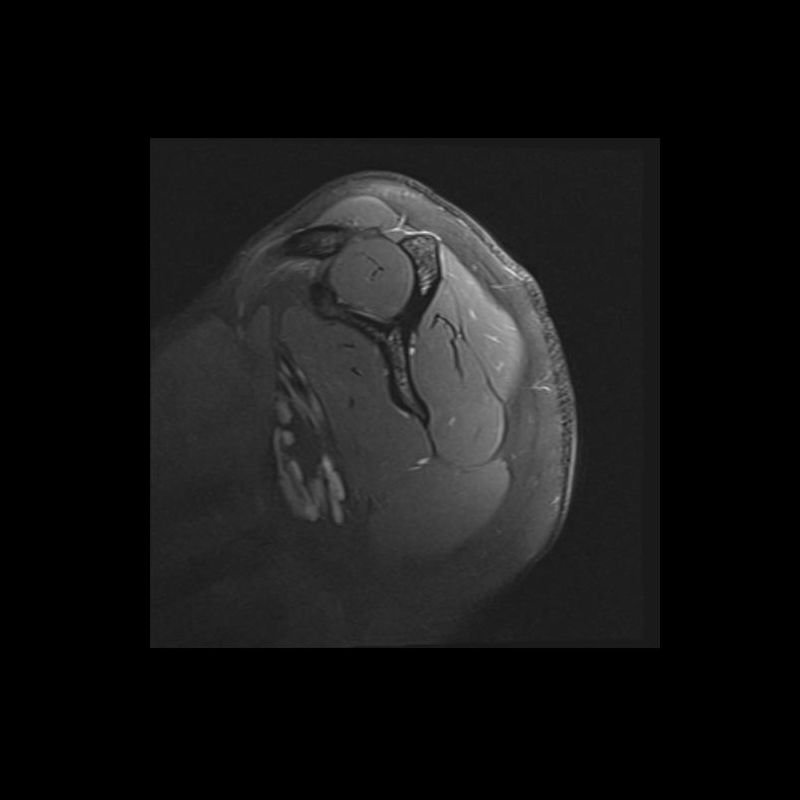

Shoulder MRI Anatomy